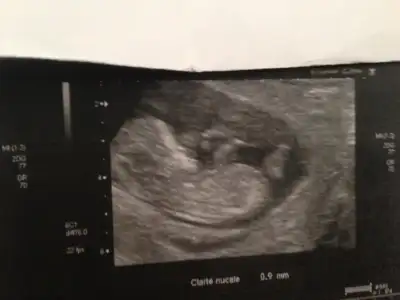

Eki Görüntüle 623587 orkidem canim benim insallah becerebildim sayende

Kesinlikle katiliyorum goruntu cok guzelse yanilma payi nerdeyse sifirMerhaba kizlar bizde esimle nub teorisine gore bakmistik 10 haftalik ken erkek diye tahmin yuruttuk ve doktor oglusumuz olacagini soyledi :)) bizimkinde cok belliydi cikintilar burdaki bazi fotogaflarda hic belli degil tahmin yurutmek zor oluyor

Merhaba)kacıncı hadtadasınız?Artıq kesin mi söyledi?Orkide size erkek mi demişti?orkdm nub teorini çöpe atma canım, kız çıktıbende başından beri kız kız diyodum yanılmadım :124:

Merhaba, ben buraya foto koyduğumda 12 haftalıktı, şu an 16 haftadayım. orkdm kız demişti, ben de kız demiştim kız çıktı:) artık kesin çünkü sallanan bişey yoktu bacak arasındaMerhaba)kacıncı hadtadasınız?Artıq kesin mi söyledi?Orkide size erkek mi demişti?

Merhaba, ben buraya foto koyduğumda 12 haftalıktı, şu an 16 haftadayım. orkdm kız demişti, ben de kız demiştim kız çıktı:) artık kesin çünkü sallanan bişey yoktu bacak arasında![]()